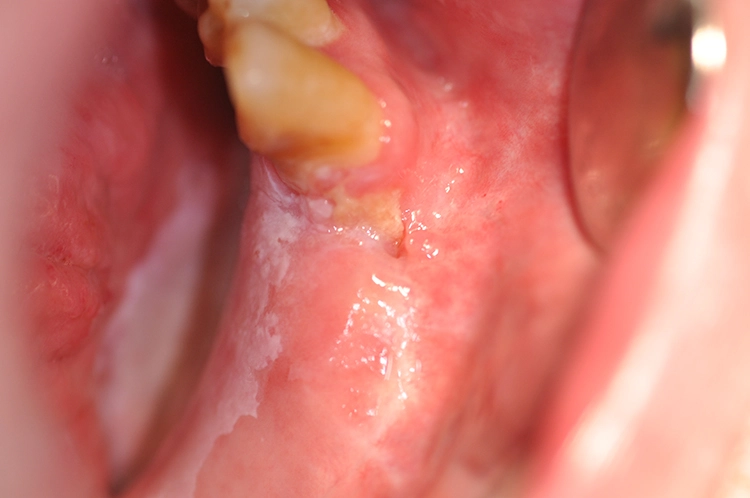

Veränderungen der Mundschleimhaut können vielfältig in Erscheinung treten. Häufig sind es entzündliche Stomatitiden, die sich einfach mit prednisolonhaltiger Salbe behandeln lassen (z.B. Dontisolon®) [2]. Leukoplakien lassen sich dagegen schwerer genau bestimmen. Sie zeigen sich als vornehmlich weiße Läsionen, die weder klinisch noch histologisch einer anderen Mundschleimhautveränderung zugeordnet werden können [3].

Die Einstufung wurde zuletzt in der WHO-Klassifikation 2017 definiert, die sich am Grad der vorliegenden Dysplasie orientiert – niedrig-, mäßig- oder hochgradige intraepitheliale Neoplasie (Englisch: Squamous Intraepithelial Neoplasia, kurz SIN 1 bis 3). Der Begriff des „carcinoma in situ“ entspricht einer SIN 3 [4].

Tritt innerhalb von 2 Wochen keine Besserung bzw. Ausheilung der Mundschleimhautveränderung ein, besteht der Verdacht einer Vorläuferläsion, die von einem Spezialisten histologisch auf ihre Dignität hin untersucht werden muss [1,4].